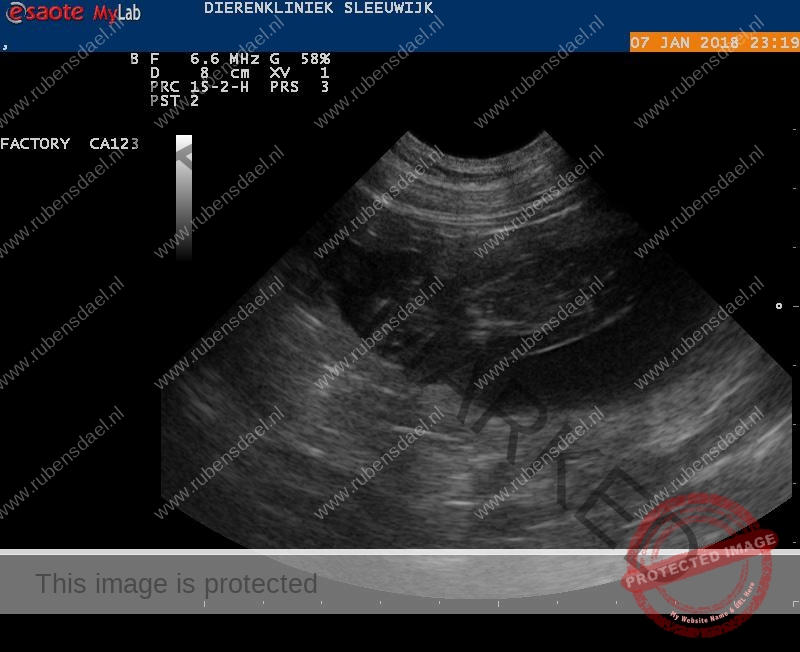

Bij het zien van de echo op het scherm riepen we gelijk “hoera” want Bryn is drachtig!

De dierenarts nam de tijd om een uitgebreide echo te doen en vertelde dat we een groot nest kunnen verwachten! Wat zijn we blij met deze dekking uit de combinatie Bryn x Floris sr.